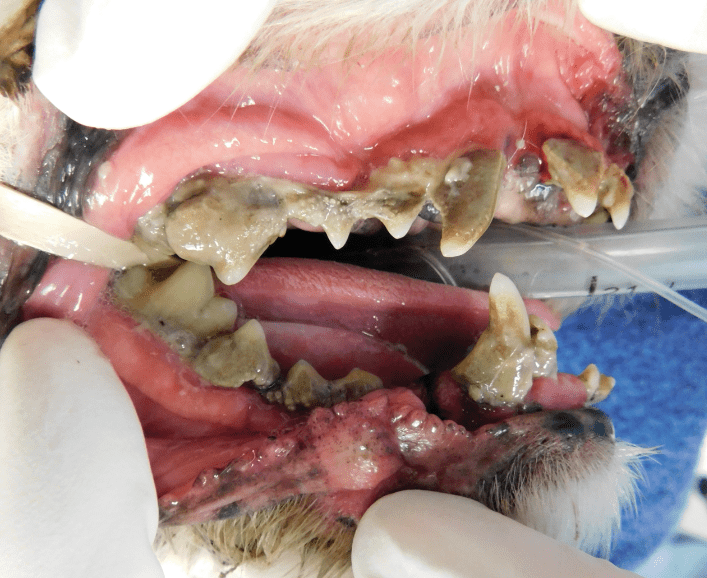

Surgical Extraction of Diseased Teeth

Periodontal disease is extremely common in dogs and cats. Over 80% of dogs and cats over two years of age have some degree of periodontal disease. Periodontal disease is best prevented by yearly professional dental cleanings starting at two years of age and at home brushing at least three times weekly. Brushing should begin at a very early age to allow your new pet to get used to regular brushing. In severe cases of infection or periodontal disease, the teeth may need to be surgically extracted. Extractions should always involve x-rays of the tooth first, as many teeth have multiple roots or may be diseased below where the eye can see. Extracting larger teeth in animals requires oral surgery, equivalent to removing wisdom teeth in people. It is vital that all of the tooth and roots be removed for the periodontal infection to resolve. In cases of important teeth with mild to moderate periodontal disease, multiple periodontal treatments can be offered to help save these teeth.

Therapy for Oral Inflammation

Dogs and cats can sometimes have severe inflammation of the mouth and gingivitis. It is not always known what the exact cause of this painful condition is, but it can be successfully managed. In cases of severe inflammation, some or all of the teeth may need to be surgically extracted. This often greatly improves the pain and inflammation in the mouth in over 80% of patients. In severe cases that do not respond to full mouth extractions, medical management can help reduce or resolve the inflammation and pain.